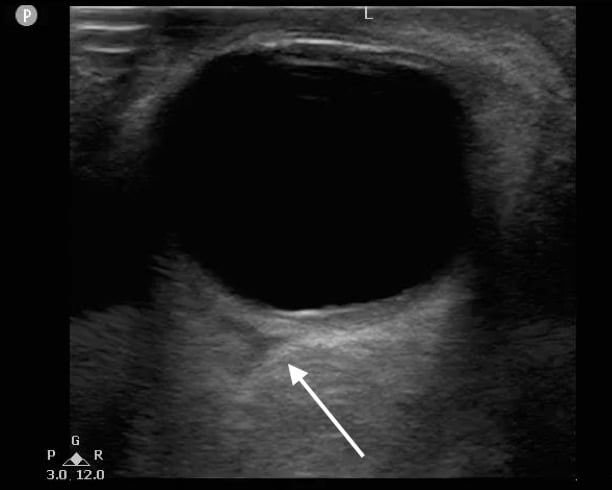

- Figure 12. Triangular hypoechoic area (white arrow) suggestive of retrobulbar hematoma also known as “Guitar Pick Sign.”